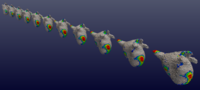

Longitudinal Shape Analysis for AFibThe shape evolution of the left atrium in the atrial fibrillation patiens is studied longitudinally to reveal the difference between recover group and the AFib recurrence group. More... | |